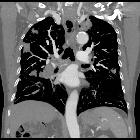

case of pulmonary embolism. Follow up CT shows a marked increase of the pulmonary artery tree involvement.